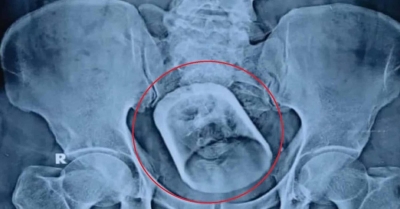

Άναυδοι οι γιατροί - Άντρας βρέθηκε με γυάλινο ποτήρι στο έντερο: «Έπινα τσάι και το... κατάπια» 06/04/2023 - 13:04 - Διεθνή